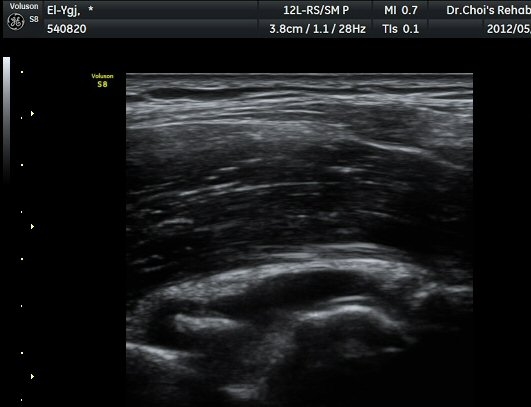

ÆÈ²ÞÄ¡ ³»Ãø Á¾´Ü¸é°ú Ⱦ´Ü¸é°Ë»ç¿¡¼­ ȰÂ÷ ¾Õ°ú °¥°í¸®µ¹±â¿Í(coronoid fossa)¿¡ ¼ö¾×Àú·ù°¡

°üÂûµÇ°í °¥°í¸®µ¹±â¿Í¿¡ °í¿¡ÄÚ »À µ¢¾î¸®°¡ °üÂûµÈ´Ù(±×¸² 2, 3).